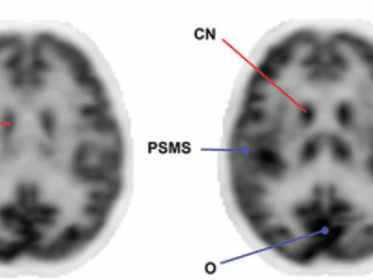

PET Cerebrale con FDG per la diagnosi di demenza e pattern cerebrali

La diagnosi precoce e la caratterizzazione delle sindromi demenziali rappresentano una sfida crescente in ambito medico. In questo contesto, la Tomografia a Emissione di Positroni (PET) con FDG si è affermata come un biomarker di imaging di importanza strategica. Questa metodica permette di rilevare i disturbi neurodegenerativi in una fase più precoce rispetto ad altre…